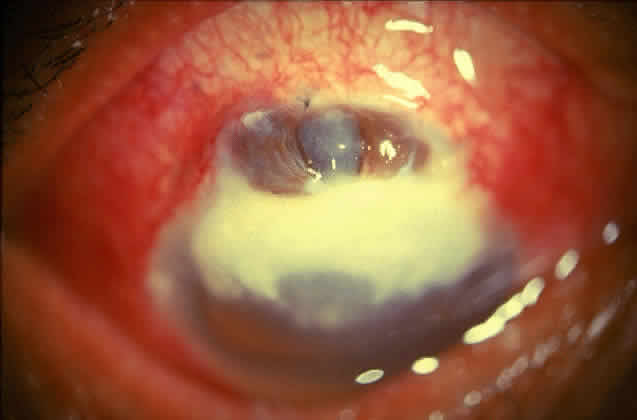

Delay in diagnosis, the relative ineffectiveness of antifungal agents in most parts of the world, and the nonavailability of these drugs hinder prevention and management (Fig. 3).

Fig. 3. Advanced stage of corneal ulcer caused by Fusarium solani.